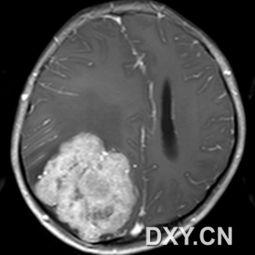

四、脑肿瘤图片的解读

接下来,让我们一起来解读一下这些脑肿瘤图片。

1. 肿瘤的形态:良性肿瘤通常呈圆形或椭圆形,边界清晰;而恶性肿瘤则形态不规则,边界模糊。

2. 肿瘤的大小:肿瘤的大小可以反映其生长速度和恶性程度。

3. 肿瘤的位置:肿瘤的位置可以影响其症状和治疗效果。

4. 肿瘤的密度:肿瘤的密度可以反映其成分,有助于判断肿瘤的性质。